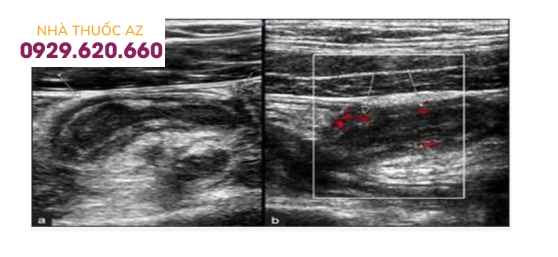

Siêu âm đau bụng 1⁄4 dưới phải do viêm ruột thừa